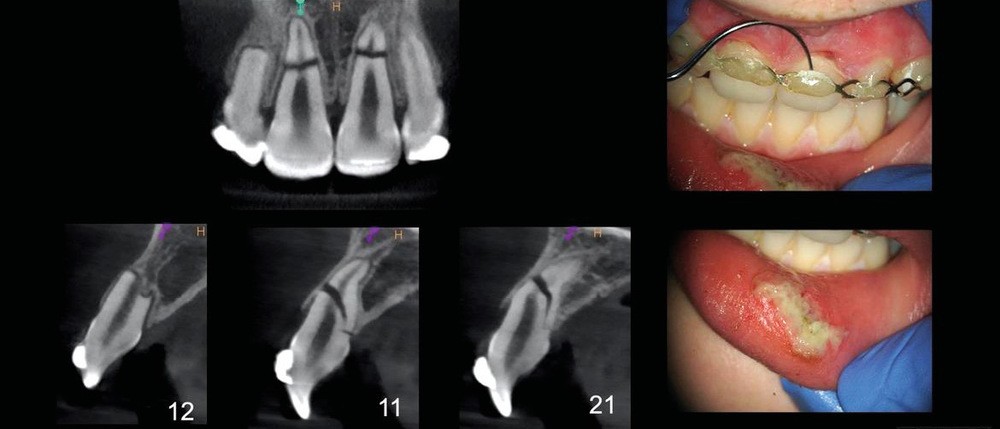

Grâce à ce cliché radiologique, une décision thérapeutique éclairée peut être prise. A savoir : la situation ne peut pas rester comme telle si l’on souhaite obtenir une guérison. Il est alors nécessaire de déposer la première contention et de repositionner convenablement les dents sous anesthésie locale aussitôt que possible puis de placer une nouvelle contention. Cela est indispensable afin d’espérer un pronostic favorable (fig. 4).